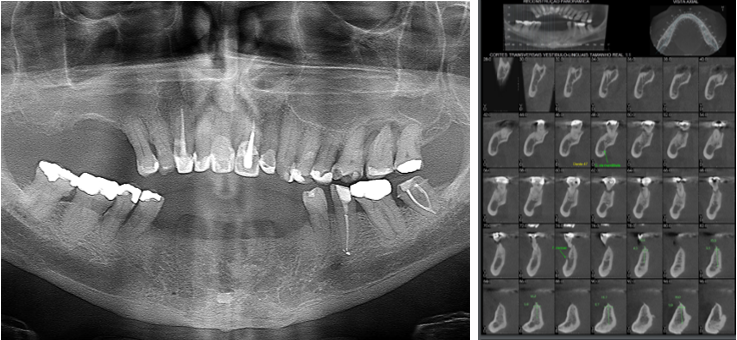

O planejamento reverso em Implantodontia assume importante papel no posicionamento 3D dos implantes. Nesse sentido, relatamos esse caso de ausência dos dentes anteriores inferiores (31/32/33/41/42/43) de um paciente usuário de prótese parcial removível que tinha o desenho de usar uma prótese fixa sobre implantes, como ilustrado nas imagens abaixo.